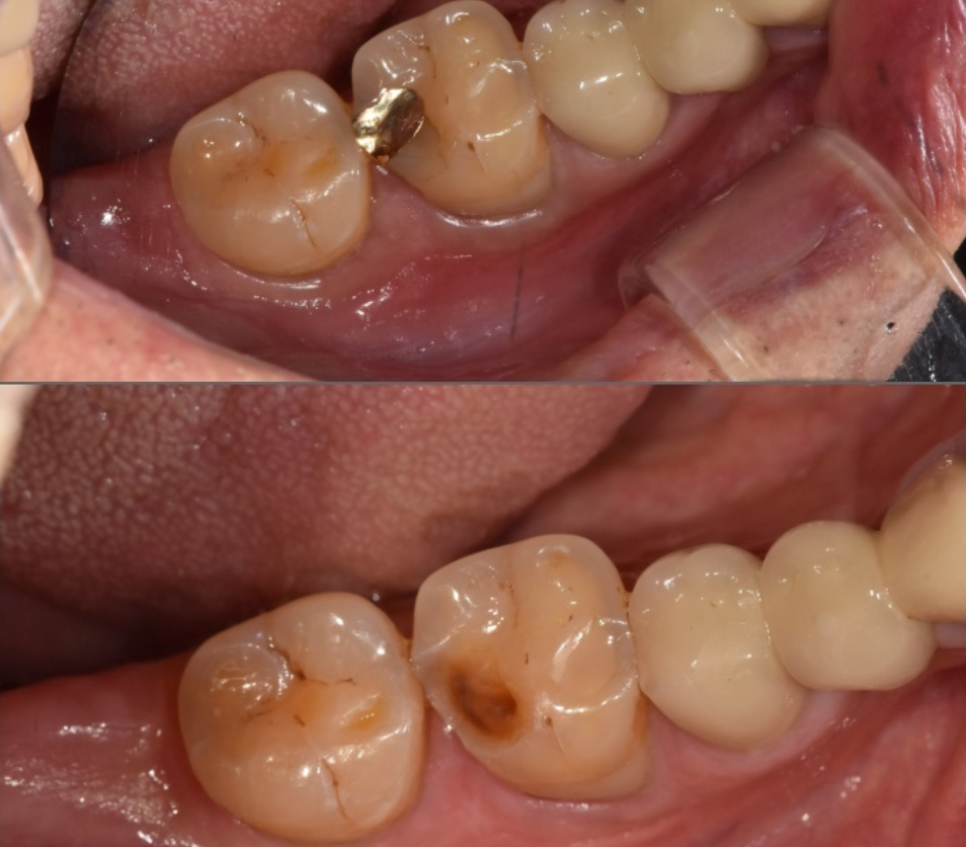

본격적인 신경치료를 위해

먼저 와동형성 과정을 거쳤습니다.

용어가 조금 생소하시죠?

쉽게 말해,

치아 내부에 숨어 있는 신경관에

안전하게 도달하기 위해

치아머리 부분에 작은 입구(구멍)를

만드는 작업을 뜻해요.

240229

이 구멍을 통해 치아 내부를 들여다보니,

겉에서 보던 것보다 실금이 더 깊고

선명하게 이어져 있네요..

자칫하면 뿌리까지 이어져

치아가 반으로 갈라질 수도 있는 상황..

환자분의 통증을 잡기 위해

오염된 신경을 깨끗하게 제거하고,

240308

세균이 침투했을지 모를 신경관 내부를

소독하는 과정을 2~3번에 걸쳐

꼼꼼히 진행했어요.